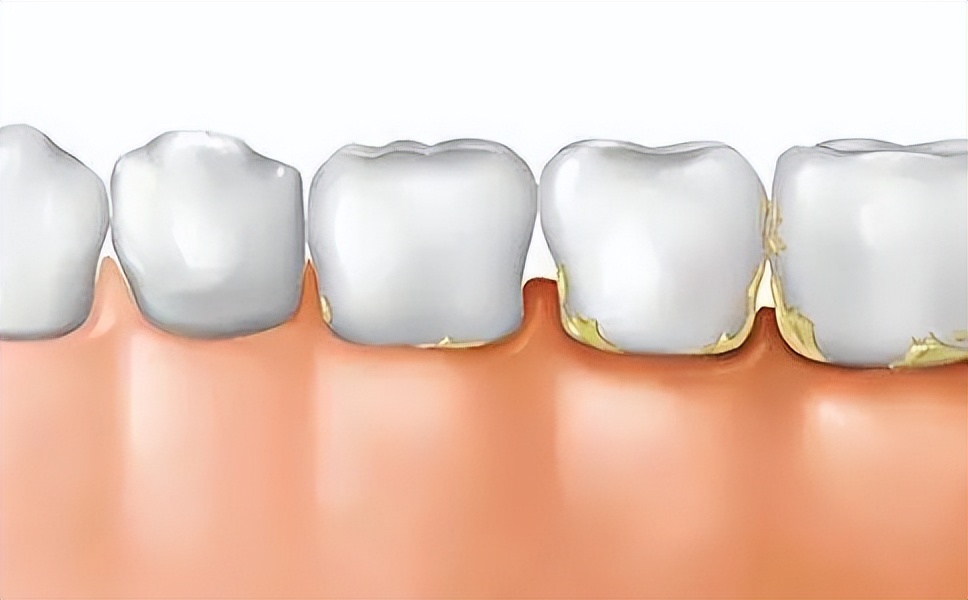

牙结石是沉积在牙齿表面上的乳白色软垢,后因逐渐的钙化而变硬。其实每个人一定程度上都存在牙结石,时间越久,牙结石就会越来越厚。并且,牙结石一般不会自行脱落。

在牙缝和靠近牙龈沟的位置,很容易【藏污纳垢】,这个位置又不容易被清洁,因此口腔中就产生了细菌,长此以往就形成了【牙菌斑】。如果牙菌斑停留在牙齿上不及时清除,慢慢得沉积越来越多就会钙化形成牙结石。